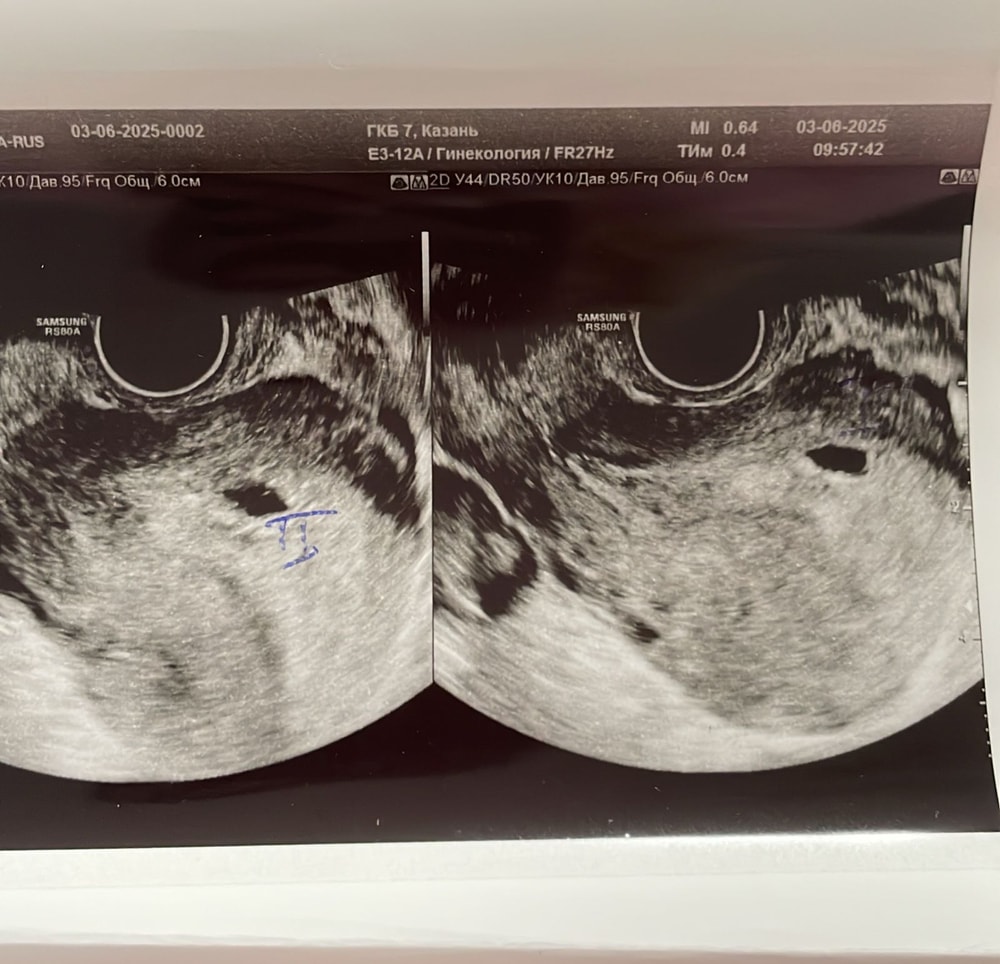

Девочки,это двойня?

Срок маленький,эмбрионсиклв еще не видно,поэтому пока врач ставит под вопросом 🙏🏻 из вашего опыта,что скажите? Срок 5-6 недель

В 5-6 недель рано, не переживайте, в 6-7-8 недель все точно ясно будет. Сами сейчас с врачами гадаем 1 или 2))) но у меня нет 2ого ПЯ, пока не видно, как они говорят, а вот эндометрий, увеличенное ПЯ и желтые тела с кровотоком, рост хгч косвенно Ре говорит указывают на многоплодную беременность))) так что ждем срока побольше, мы с вами прям рядышком по неделькам👶🏻👶🏻